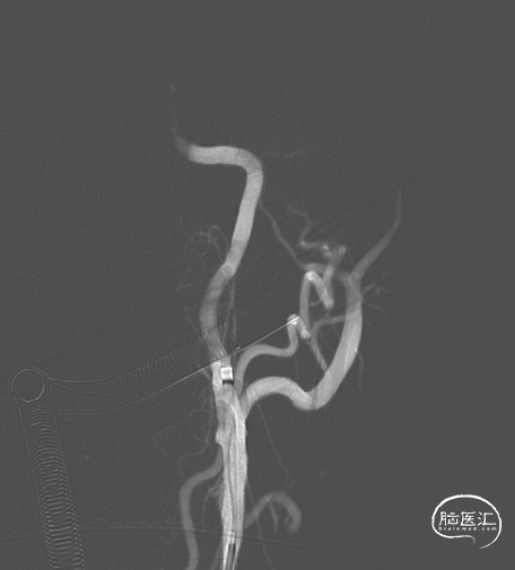

血管闭塞。

CTA重建。

右侧颈内动脉无代偿血流。

造影提示:左侧颈内动脉交通段闭塞。